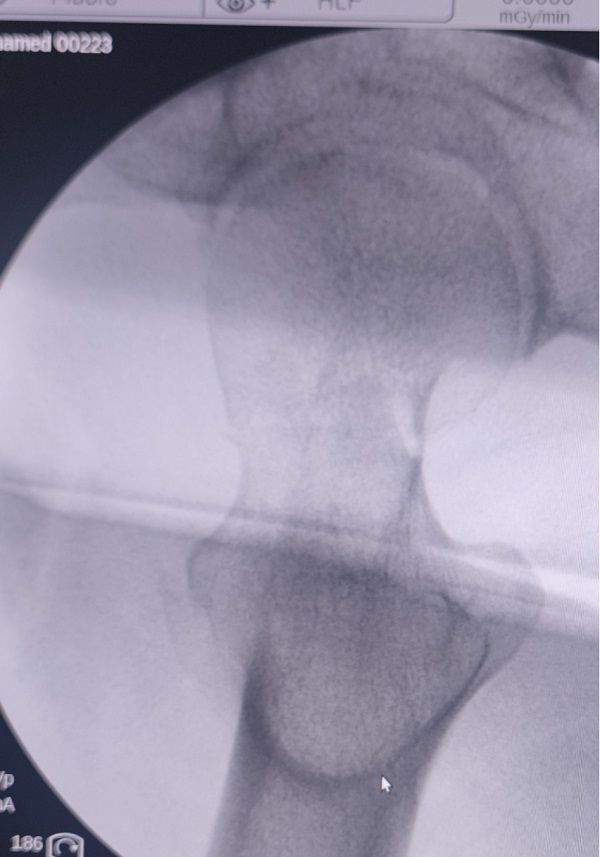

49岁的段先生在工地干活时不幸摔伤,被工友紧急送来咸阳骨科医院创伤骨科就诊。急诊拍片显示左侧股骨颈头下型、GardenⅣ型骨折。造成该类型骨折的暴力大,骨折移位严重,骨折周围血液循环受损严重,骨折不稳定,治疗效果差。伤后影像学检查结果如下:

术前X线片:

术前CT :

牵引床下复位效果: